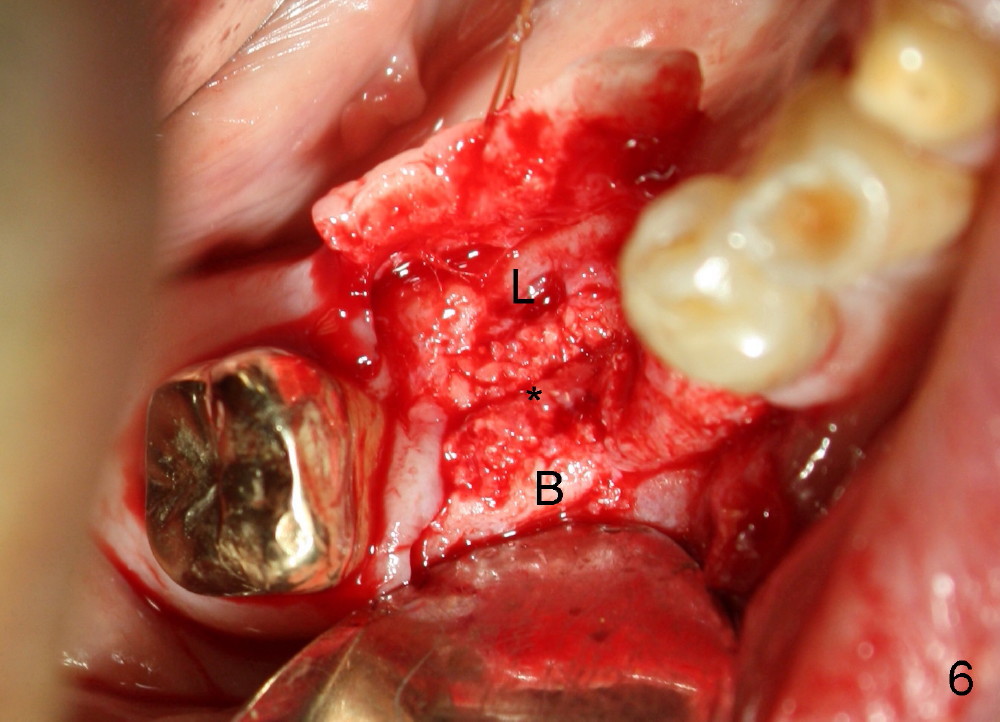

Three months later, the B-L width at the site of #29 is significantly reduced (Fig.4). Upon X-ray exam, there is decreased bone density between these two sockets (Fig.5 *). Socket preservation seems not to live its expectation. The obvious advantage is formation of callus-like bone in the molar socket (Fig.6 *, between the buccal (B) and lingual (L) plates). The significant decrease in the buccolingual width at the site of #29 is associated with buccal plate crack during implantation (Fig.7 *). At the site of #30, the lingual plate is so low that there is implant thread exposure (Fig.8 <). Mixture of autogenous bone (harvested from drilling with Bicon reamers) and synthetic bone (Osteogen) is placed mainly buccal to the implant #29 and lingual to #30 (Fig.9), followed by collagen membrane. Bone density between these two implant increases due to the bone grafting (Fig.10 *, as compared to Fig.5). In fact, the implant at the site of #29 is found loose 1 month postop.